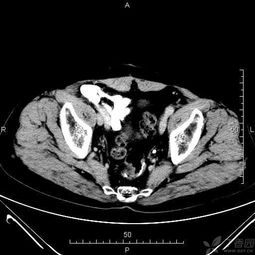

一,檢查前病人禁食即可.二.腹部檢查之前不能做其它造影檢查,尤其不能用鋇劑行消化道造影,以免腸內(nèi)殘留的造影劑形成偽影,影響ct圖像質(zhì)量,從而導致誤診.

各部位增強掃描及腹部平掃者,檢查前至少禁食四小時.

腹部檢查者,檢查前三日內(nèi)不食重金屬類物及不作鋇餐檢查.

需增強掃描者,檢查前需禁食一餐且三日內(nèi)不食重金屬類物及不作鋇餐檢查.